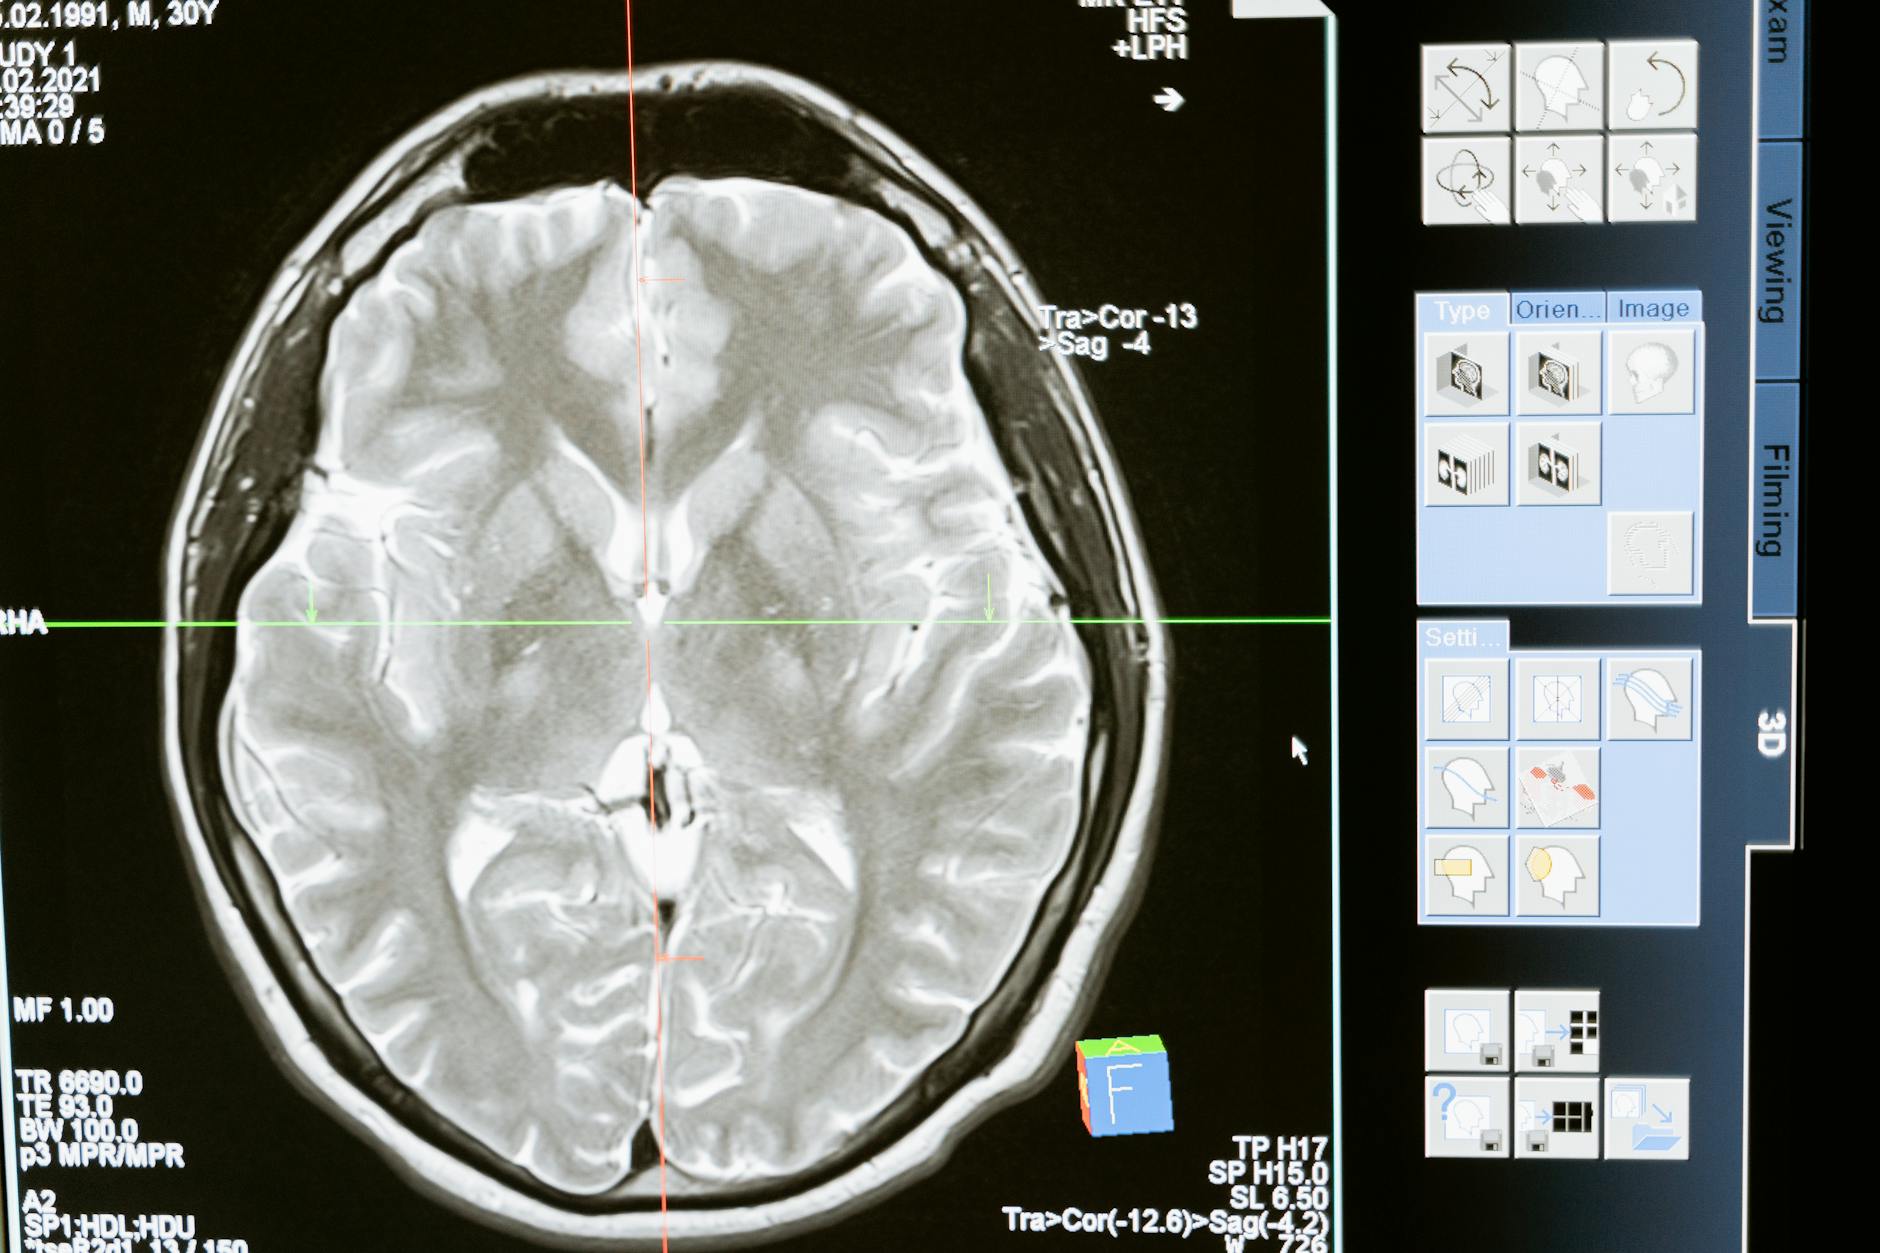

Un nuevo modelo de inteligencia artificial superó a radiólogos en la detección de signos tempranos de cáncer de páncreas en tomografía computarizada (TC), según una investigación difundida por Health Imaging. El resultado refuerza uno de los frentes más prometedores de la IA aplicada a la imagen médica: identificar lesiones pequeñas, en fase pre-clínica, en una de las neoplasias más letales y silenciosas de la oncología.

Los modelos de IA más recientes para detección de cáncer de páncreas siguen tres líneas. La primera entrena redes convolucionales profundas (CNN) en TC con contraste en fase pancreática para identificar lesiones focales y diferenciarlas de tejido sano. La segunda usa arquitecturas de segmentación (U-Net y variantes) para delinear parénquima, ducto pancreático y posibles lesiones, transformando la lectura en mapas cuantitativos. La tercera combina ambas en pipelines multitarea: el algoritmo segmenta el páncreas, mide características como volumen, atenuación y dilatación ductal, y entrega un puntaje de sospecha.

El diferencial es la sensibilidad para patrones pre-clínicos: el algoritmo aprende, a partir de cohortes retrospectivas, cómo cambia la glándula meses antes del diagnóstico clínico. En estudios publicados en los últimos años, este tipo de pipeline alcanzó sensibilidad cercana o superior a la de radiólogos experimentados para tumores menores de 2 cm — históricamente el punto más difícil de la rutina.